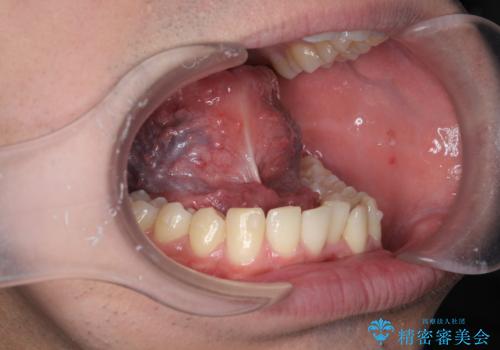

[舌小帯の形成術] 舌の動きが悪い 滑舌を改善したい!

滑舌の改善 舌小帯の形成術